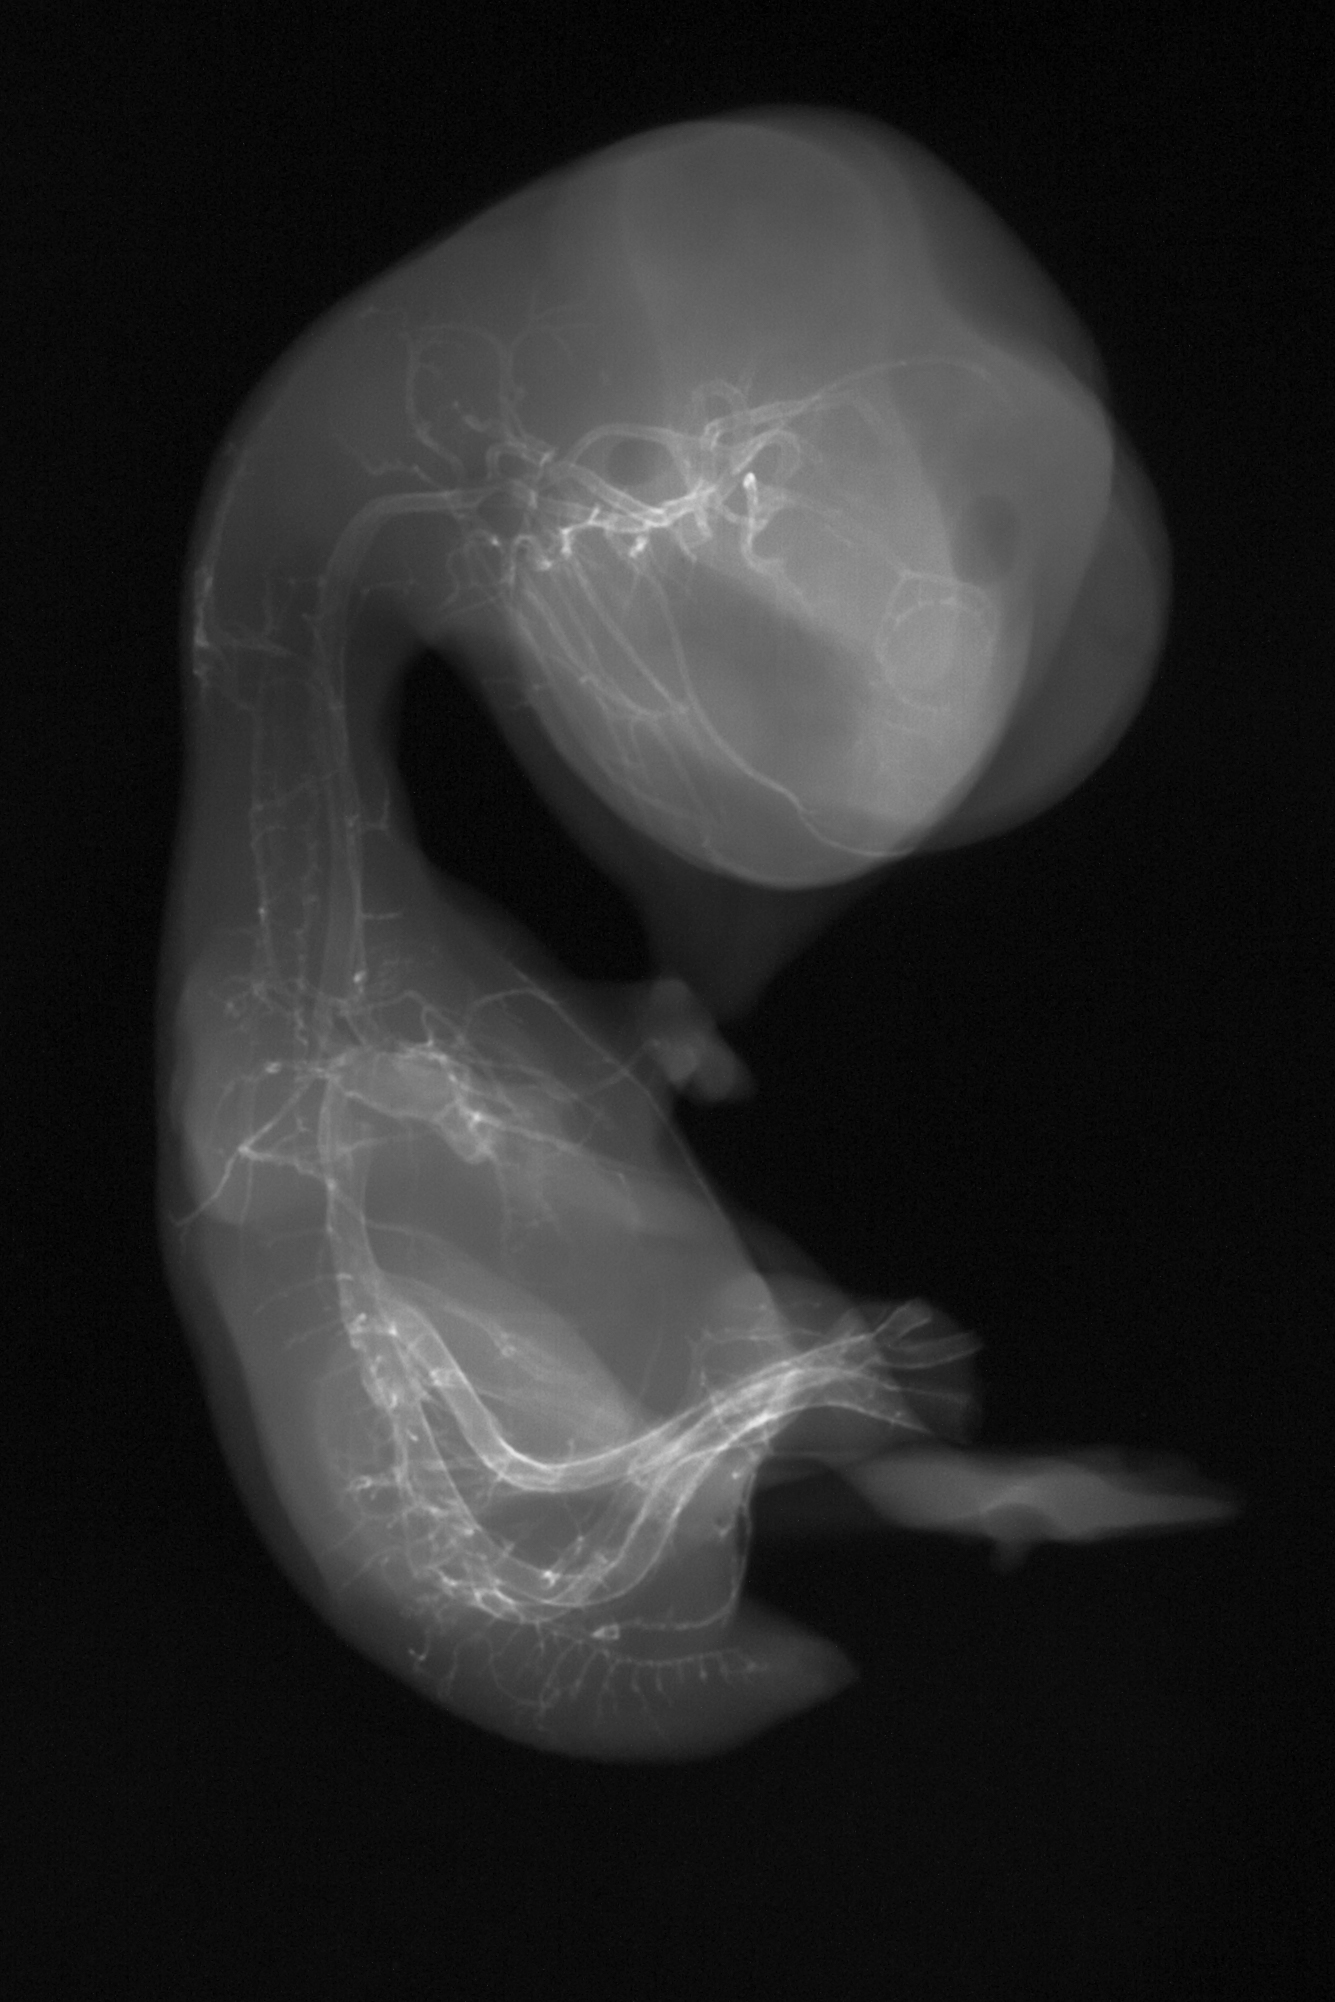

Chick Embryo Microangiography

Hamburger-Hamilton (HH) Stage 35 (approx. 8.5 - 9 days)

X-Ray Micrographs